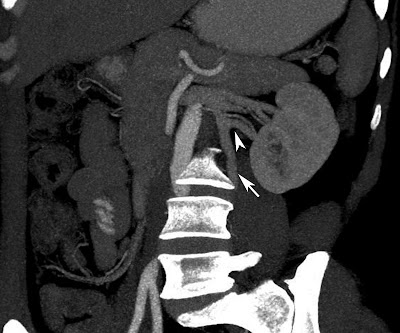

Axial CT of kidneys in a 29 year old male showing small exophytic fat attenuation lesion in the left kidney (arrow) suggestive of angiomyolipoma.

Zoomed picture of the above showed image better shows the lesion.

CT Scan: Well defined fat attenuation lesion as shown in our case. CT angiography may be helpful to identify the aneurysms which predict the fatal hemorrhage.